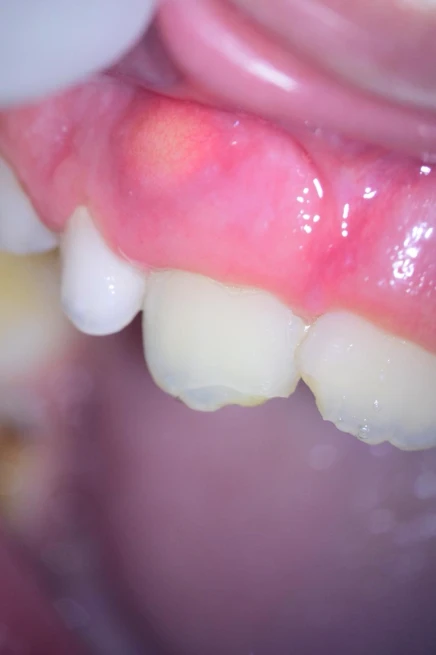

Paciente com 8 anos de idade, compareceu ao consultório com fístula em região vestibular e leve escurecimento em dente 11 (figura 1). Foi realizado o exame clinico e radiográfico (radiografia periapical) na qual foi observado o ápice aberto desse dente (figura 2). No teste de sensibilidade com gás refrigerante o dente apresentou vitalidade negativa.